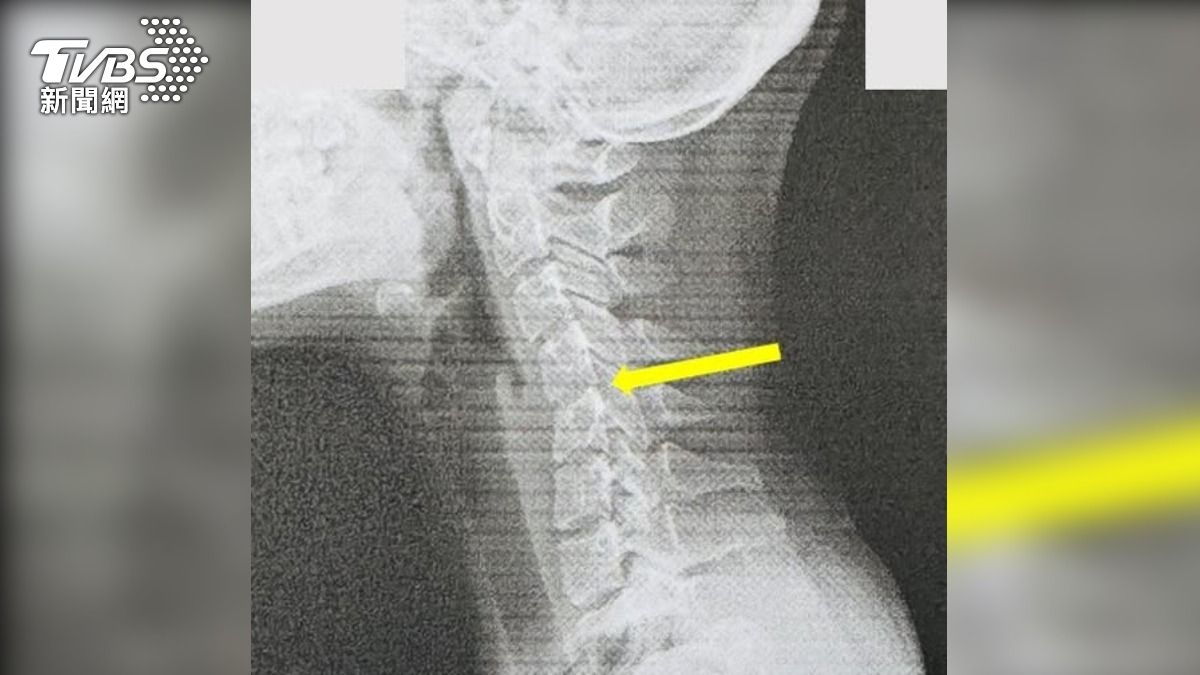

根據《TVBS新聞網》報導,彰化一名年僅20歲的女大學生因沉迷滑手機,加上睡眠姿勢不正確,近期出現頭部疼痛及頸部僵硬等不適症狀。經醫師檢查後驚見她的頸椎弧度已消失,甚至發生滑脫現象,身體狀況竟與60歲中老年人無異。

員榮醫院神經內科專家表示,健康的頸椎應該呈現「C型」弧度,這樣的設計能有效分散頭部重量。不過,頻繁低頭使用手機會讓頸椎負擔大幅增加。

人類頭部重量約3至4公斤,當頭部下傾30度時,頸椎需承受約18公斤的壓力;若低頭角度達到60度,壓力更飆升至27公斤,相當於頸部要扛起一個七、八歲兒童的重量。

醫師進一步解釋,頸椎過度退化可能引發持續性頭痛、頭暈目眩,甚至造成上肢麻痛等併發症。更嚴重的情況下還會加速椎間盤突出及骨刺生成。